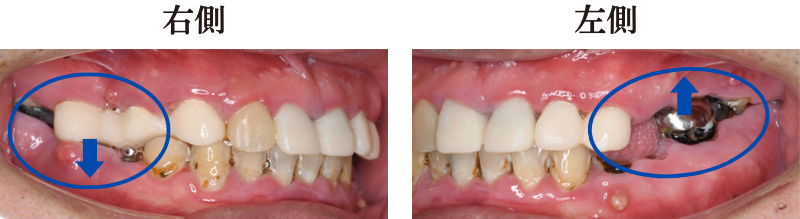

治療前の口腔内

虫歯で歯の根が残った口腔内

診察すると、虫歯が進行して歯の根っこしか残っていない歯が複数ありました。

これらの歯の状態から、単純な虫歯治療では状況を改善できないと判断。残せない歯は抜歯し、残せる歯は入れ歯を支える土台とする治療を行い、その後入れ歯の作製に取り掛かりました。

噛み合わせのバランスが

崩れた口腔内

右側は上の歯が下の歯茎まで食い込み、左側は下の歯が上の歯ぐきに食い込み咬み合わせのバランスが崩れている状態でした。

そこで、あごやあごの関節を分析する「Gerber method(ゲルバーメソッド)」という理論を取り入れてアタッチメント義歯を作製。患者さまに適した咬み合わせに調整しました。しっかり噛めるようになるだけでなく、崩れてしまった咬み合わせのバランスも整えられます。